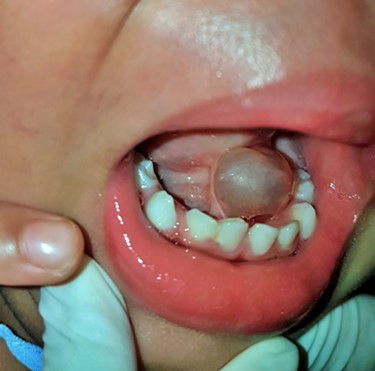

Two-year-old boy with cystic lesion at floor of month combined with ankyloglossia.

A 2-year-old boy presented with a slow growing mass under the tongue for 6 months. He was born without any anomaly. The development status was within average except delay speech due to the mass at floor of mouth. The physical examination revealed left sublingual cystic lesion measuring 1.0 × 1.0 cm. Ankyloglossia was found (Fig. 1). Cervical lymph nodes could not be palpated. Magnetic resonance imaging (MRI) demonstrated multi-lobulated cystic mass, size about 3.15 × 2.1 × 2.9 cm, which showed hypersignal intensity on T2 weighted image, hyposignal intensity on T1 weighted image, T1 fat suppression, T1 fat suppression with gadolinium involving left sublingual, submandibular, pharyngeal and parapharyngeal spaces (Fig. 2A–C). The provisional diagnosis was lymphatic or venous malformation.